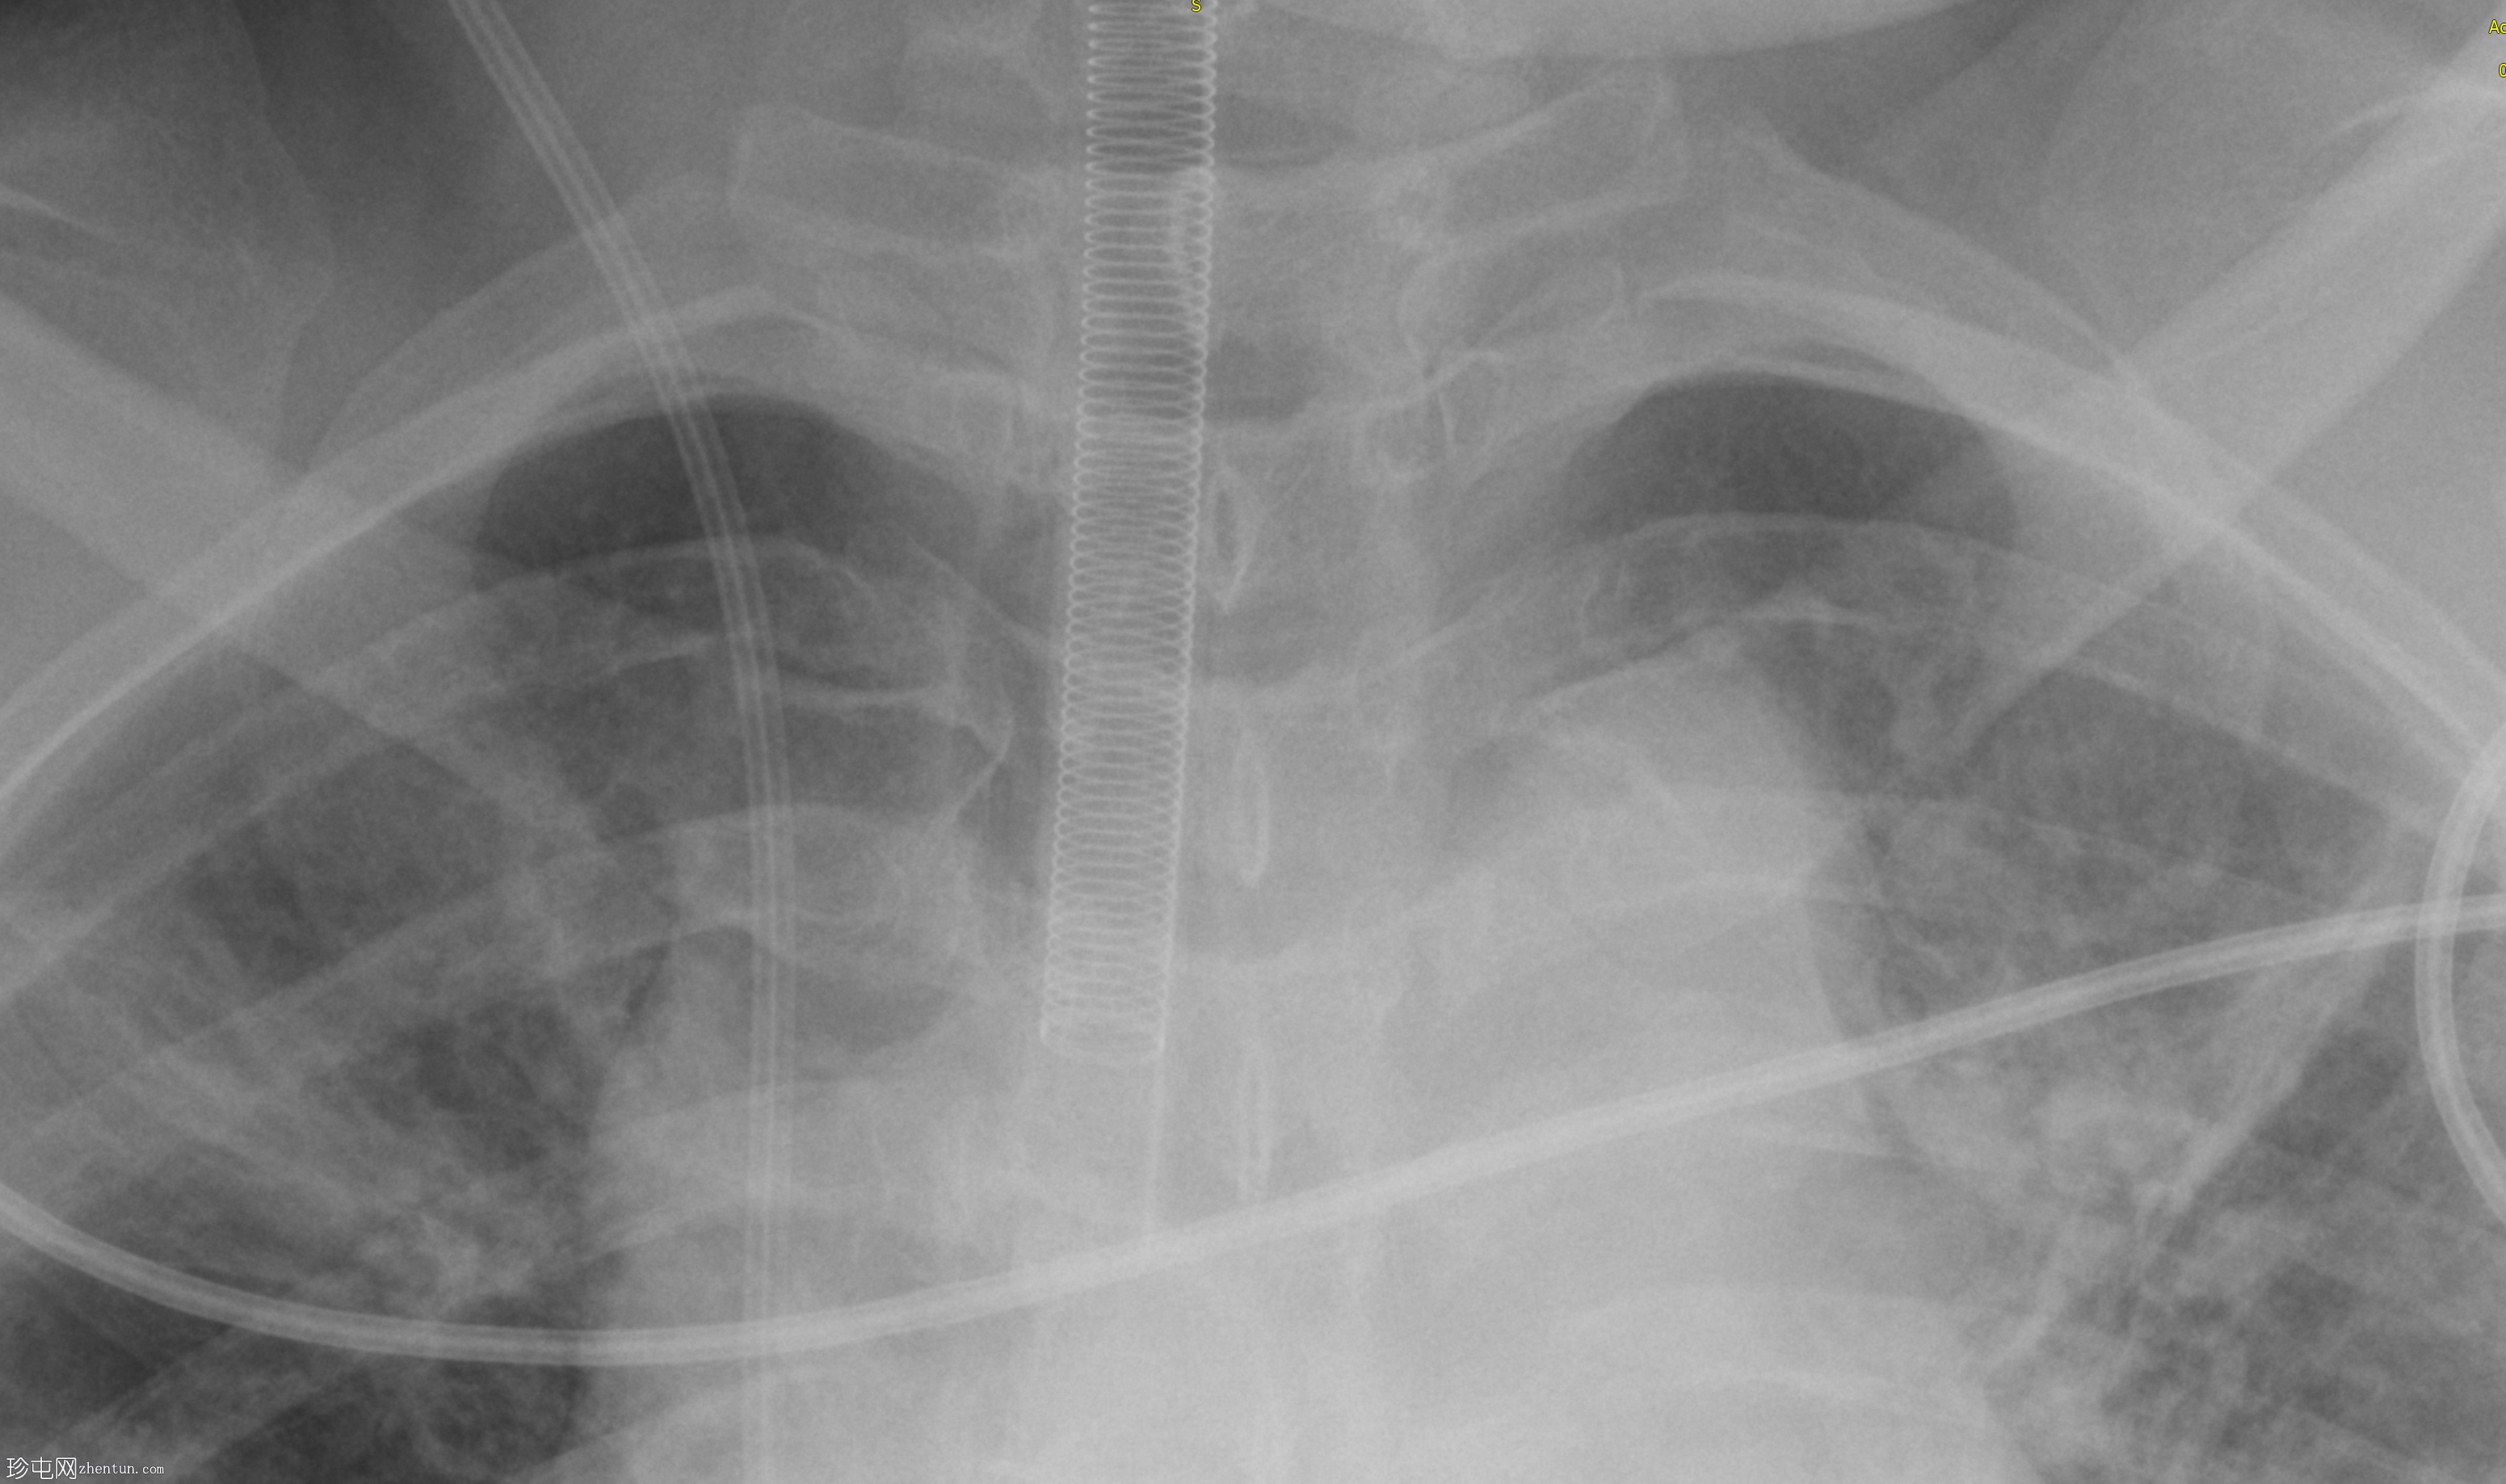

患者接受开颅手术后,现进行术后胸部X光检查,以评估导管和气管的情况。

移动式X光片显示患者吸气用力减弱,伴有预期的门充血、支气管血管纹理增多、误吸改变,以及麻醉后肺不张。心脏和纵隔轮廓正常,但图像放大。

装甲气管插管 (ETT) 位置过深,需要回缩。

注意:加强型金属导丝末端靠近气管插管尖端。

右侧颈内静脉通路中心静脉导管尖端位置过深,需要回缩。

存在重叠的心电图导联。